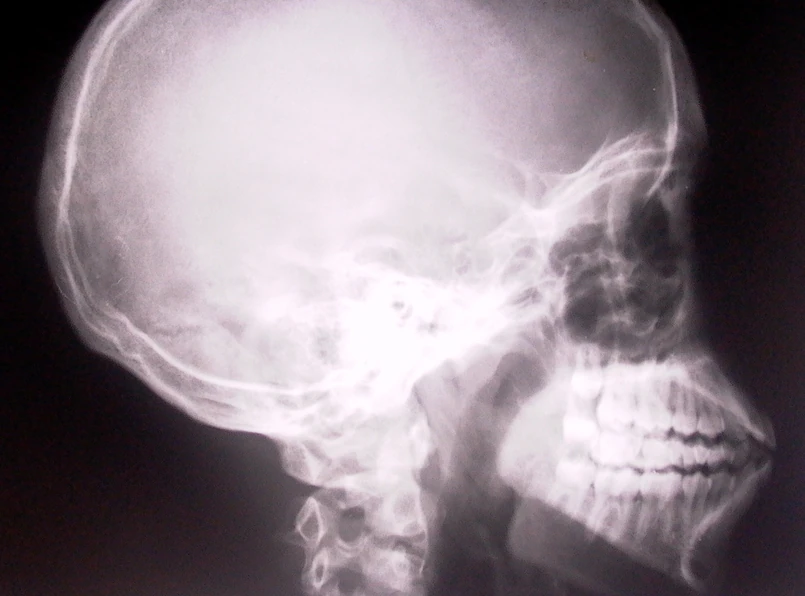

Ta historia nie powstała w głowie scenarzysty horrorów, lecz jest efektem ciężkiej pracy fińskich naukowców. Lekarze wyhodowali w brzuchu pacjenta jego własną... szczękę. Rosła ona w jego ciele przez dziewięć miesięcy. Gdy się "urodziła", naukowcy wszczepili ją do ust mężczyzny.

Fińscy naukowcy z dumą poinformowali, że udało się im wszczepić 65-letniemu mężczyźnie górną szczęką, którą wyhodowano w jego jamie brzusznej z komórek macierzystych pozyskanych z tkanki tłuszczowej pacjenta.

Następnie komórki przeniesiono na "rusztowanie" z materiału biologicznego i wszczepiono pacjentowi do brzucha, gdzie nowa szczęka rosła przez dziewięć miesięcy. "Komórki macierzyste przekształciły się w tym czasie w różne tkanki, tworząc nawet naczynia krwionośne" - cieszą się naukowcy.

Oryginalną górną szczękę pacjenta musiano usunąć z powodu nowotworu.